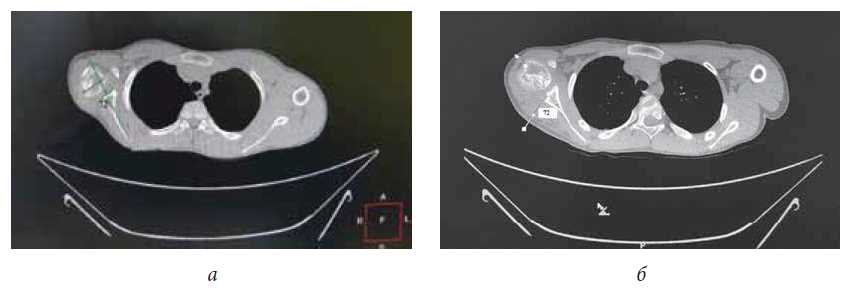

The correlation between the degree of glenohumeral dysplasia and the results of treatment was revealed: at Waters type II dysplasia after surgery, limb functionalities improved by 3–5 points; at type III, they improved by 2–4 points; and at types IV–V, they improved by 1–2 points. In patients with adduction intrarotation contracture after surgery, improvement in abduction in the shoulder joint was noted in all cases. Examination revealed that the ratios in the shoulder joint improved or remained unchanged; however, there was no remodeling of the joint surfaces (Figure 3).

Fig. 3. Results of a CT examination of the patient M., 12 years old, with the consequence of the genital injury of the brachial plexus with the intratational contracture of the right humeral joint: a - before the operation; b - 3 months after the operation